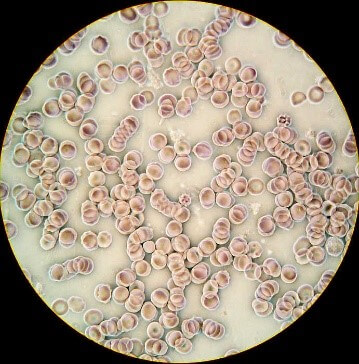

Nutritional microscopy is the science of qualitative blood observation for the purpose of

reviewing current health at cellular level.

There is no blood drawn. We use only one drop to analyze on a microscope slide.

Your blood will be analyzed in front of you and discussed immediately.

Water is essential before viewing the blood as it hydrates the cells. If the blood cells are dehydrated, the analysist will have difficulty in viewing the blood's anomalies clearly.